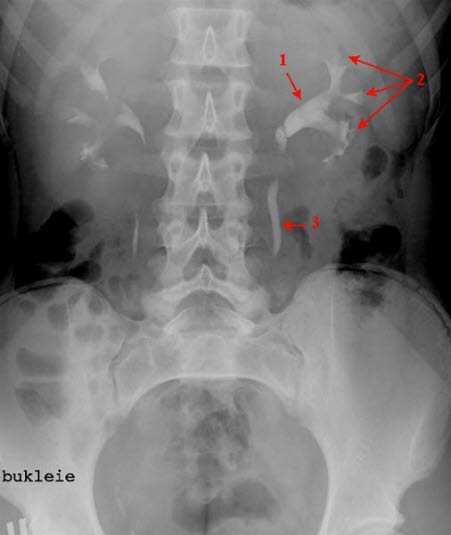

Oversiktsbilde over nyrer og urinveier i utskillelsesfase

Ca. 15 minutter etter intravenøs kontrastinnsprøytning

- Nyrebekken

- Calyces

- Ureter